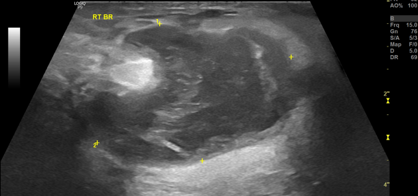

Images 1-3 below show the grossly varied appearances of galactocoele on ultrasound. All three of the following ultrasound images are lesions that were diagnosed as a galactocele after the aspiration.

Image 2